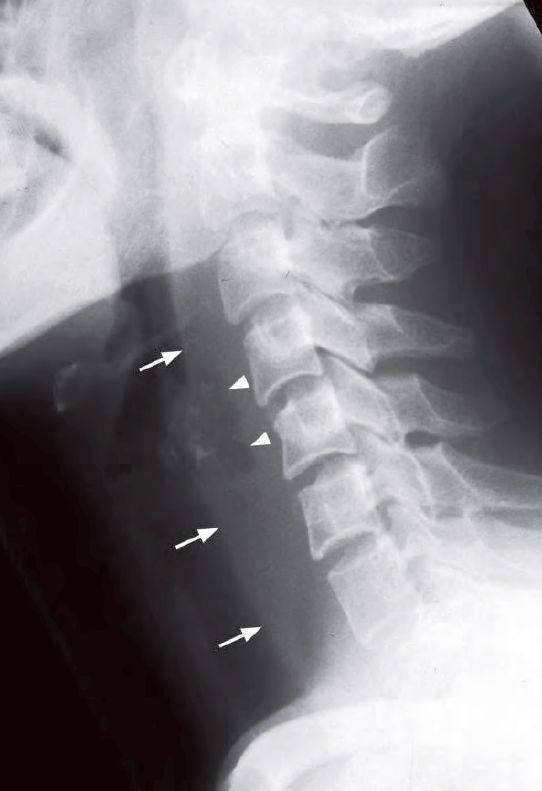

- Widened retropharyngeal soft tissues

- A localized gas locule in the retropharyngeal space

Lateral radiograph of the neck shows thickening of the retropharyngeal soft tissues (arrows) and localized gas lucency within (arrowheads) suggestive of a retropharyngeal abscess.

- Gas locules within widened retropharyngeal soft tissues on plain radiographs in the appropriate clinical setting is highly suggestive of retropharyngeal abscess.